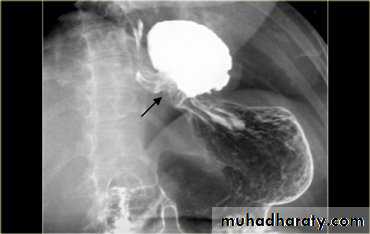

LEFT: Dilated esophagus (arrows) appears as long, well-defined structure paralleling heart RIGHT: Dilated esophagus usually deviates to right. Narrowing (arrow) at hiatus.

LEFT: CT shows dilated esophagus (arrow) that led to esophagram.RIGHT: Esophagram shows narrowing (arrow) at level of hiatus.